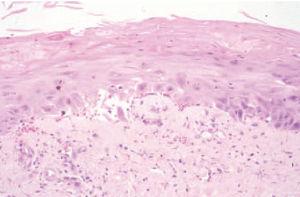

Fig. 2.Destaca una epidermis con ausencia relativa de núcleos, alteraciones madurativas de los queratinocitos y ocasionales queratinocitos necróticos. (Hematoxilina-eosina, ×100.)

En las determinaciones analíticas destacaba pancitopenia (leucocitos, 1.940; hemoglobina, 12,6 g/dl; plaquetas, 3.000), aumento de las enzimas hepáticas (transaminasas glutamicooxalacética [GOT], 54; glutamicopirúvica [GPT], 85; y gammaglutamiltranspeptidasa [GGT] 136) y proteínas totales de 5,7 g/dl. En el aspirado de médula ósea existían signos de toxicidad por metotrexato, consistentes en una médula ósea hipocelular con megacariocitos disminuidos y cambios megaloblásticos de la serie eritroide y granulocítica, con algún blasto ocasional e histiocitosis y plasmocitosis reactiva. La biopsia de una de las lesiones eritema-tosas violáceas de la pierna derecha mostraba una epidermis constituida por células de citoplasma amplio, con ausencia relativa de núcleos, importantes cambios madurativos, imágenes de atipia celular y algunas mitosis (fig. 2). Asimismo se observaba una discreta degeneración hidrópica vacuolar de la capa basal y escasos infiltrados inflamatorios linfocitarios de distribución perivascular. Focalmente se encontraban imágenes de metaplasia escamosa en los conductos ecrinos. Se suspendió el metotrexato y se instauró tratamiento con ácido folínico, imipenem y factor estimulante de colonias de granulocitos (G-CSF), con rápida mejoría clínica y analítica. Posteriormente el paciente ha presentado nuevos brotes de psoriasis, pero no se ha reintroducido el metotrexato.